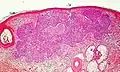

There are mainly three patterns of aggressiveness, based mainly the cohesion of cancer cells:[31]

| Low-level aggressive pattern | Moderately aggressive pattern | Highly aggressive pattern |

|---|---|---|

|